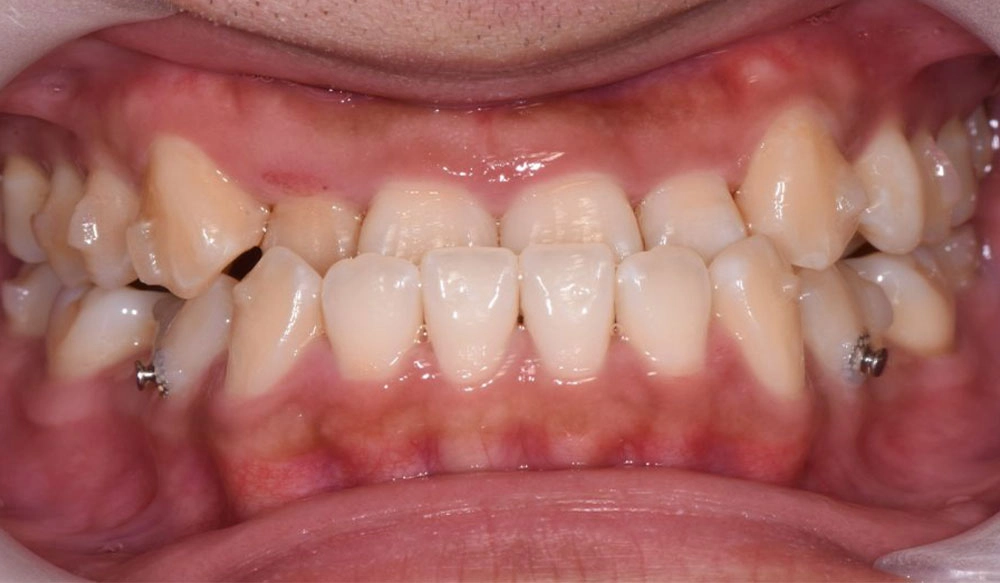

Extraction

Extraction is the removal of one or more teeth when a large amount of space needs to be created to align and create a correct occlusal relationship between the remaining teeth.

Patient Information:

Age: 16

Gender: Female

Invisalign Treatment Option: Invisalign Comprehensive

Total Treatment Time:

16 months